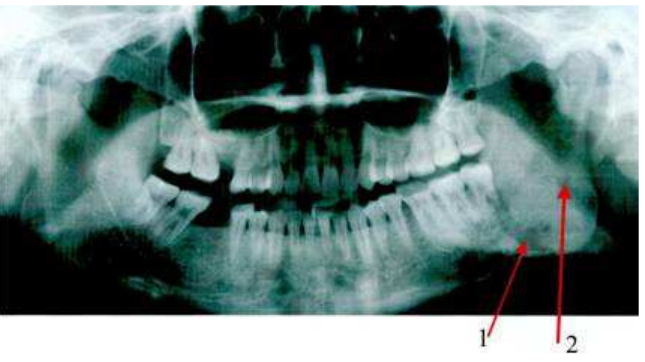

77.下圖X光片所呈現的影像,1與2箭頭所指的最可能為下列何者?

(A)1是骨折的影像,2是上呼吸道的影像 (B)2是骨折的影像,1是上呼吸道的影像 (C)1和2都是上呼吸道的影像 (D)1和2都是骨折的影像